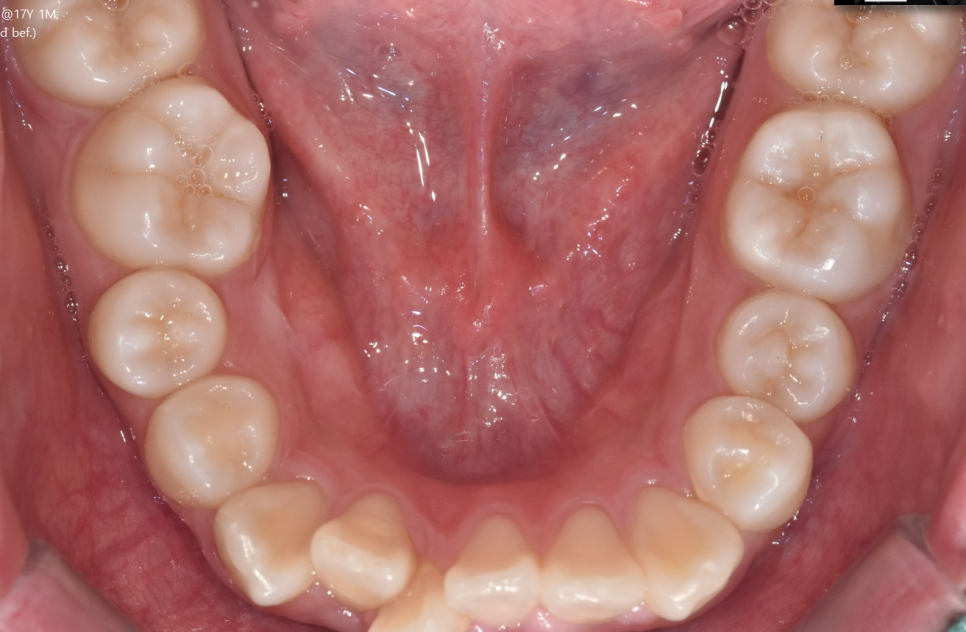

교합 상태, 치아 배열 상태를 확인하기 위해

5분할 포토라 불리는 구강 내 사진을 찍고

뽄도 뜹니다.

교정 모델을 만들기도 하며

이 과정에서 구강 스캐너가 동원되기도 합니다.

앞으로 교정을 통해 치아가 어떻게 움직일지 예측합니다.